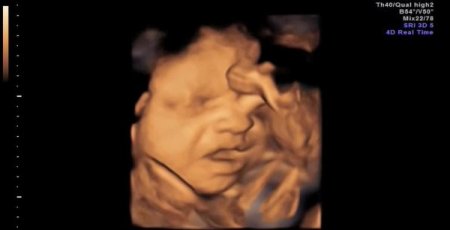

Bilim insanları, 4 boyutlu tarama yöntemiyle ultrasonda ilk kez anne karnındaki bir bebeğin esnemesini kaydetti.

İngiltere’deki Durham Üniversitesi Psikoloji Departmanı’nın, sağlık ve bilim alanında önemli makalelere yer veren PLOS ONE dergisinde yayınlanan araştırma sonuçlarına göre, 15 sağlıklı bebekte görülen yarım ağız açma hareketinin ‘esneme’ olduğu belirlendi. Doğumdan önce bebeklerin hıçkırdıkları, yutkundukları ve gerindikleri biliniyordu. Ancak esnemeleri ilk kez bu kadar net bir şekilde tespit edildi. Esnemenin, bebeğin sağlığını gözlemlemede yeni ve önemli bir ipucu olacağı düşünülüyor.

Reissland ve ekibinin gözlemi, gebeliğin 24 ve 36. haftaları arasındaki 8 kız ve 7 erkek bebekte yapıldı. Esnemenin 28. haftadan itibaren azaldığı, erkek ve kız bebeklerde önemli bir farklılığın olmadığı ortaya çıktı. CİHAN